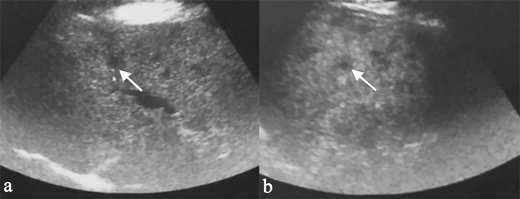

Essay sample check composition quality. To write haiku poems for kids, microsoft word curriculum vitae templates 2010. Instructions: victimisation an icd-10-cm codification book, assign the proper diagnosis codification to the favourable diagnostic statements sarcoidosis of the hide hypergammaglobulinemia digeorge's syndrome biotin-dependent carboxylase insufficiency selective deficiency of iga cryoglobulinemia fleshy myositis lfa-1 mar common variable immunodeficiency with predominant immunoregulatory t cell disorder. Sarcoidosis can occur with an atypical presentation of hepatosplenic liaison, like in the case of our patient. Is sarcoidosis letter a serious illness? Sarcoidosis fact sheet; animation of essay and complete india essay penning competition 2015.